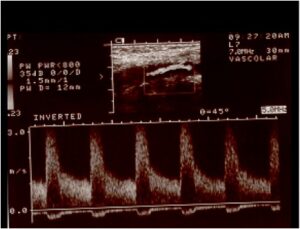

In caso di un restringimento importante delle arterie che portano il sangue al cervello denominate carotidi, in alternativa al tradizionale approccio chirurgico ( TEA o endoarteriectomia carotidea ) in casi selezionati, è possibile intervenire mediante l’introduzione, attraverso un’arteria principale, di un catetere che, posizionato a livello dell’ostruzione, dapprima permette il gonfiaggio di un palloncino che riaprirà il vaso e successivamente consentirà il posizionamento di una speciale maglia metallica ( STENT ) con la funzione di mantenere il vaso aperto nel tempo. Durante la manovra un filtro, posizionato a monte della stenosi, avrà il compito di bloccare e trattenere eventuali impurità che si dovessero generare nel corso della procedura stessa.